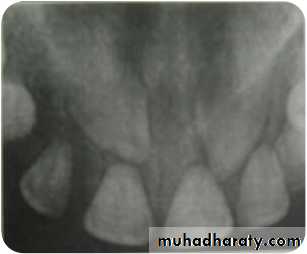

OPG

Panoramic radiographs are basic radiograph

for assessment of impacted teeth•

•

Tooth position whether deep or shallow

General orientation horizontal or inclined

mesially/distallyRelationship with neighbouring teeth

Risk of their transpositionPresence or absence of apical resorption of

roots of adjacent teeth

53

When mesio distal width of canine crown was

1.5 times larger (i.e. 15% larger) than theadjacent central incisor, then the canine is

palatally placed

This is only true in cases where canine should

not be at a higher level55